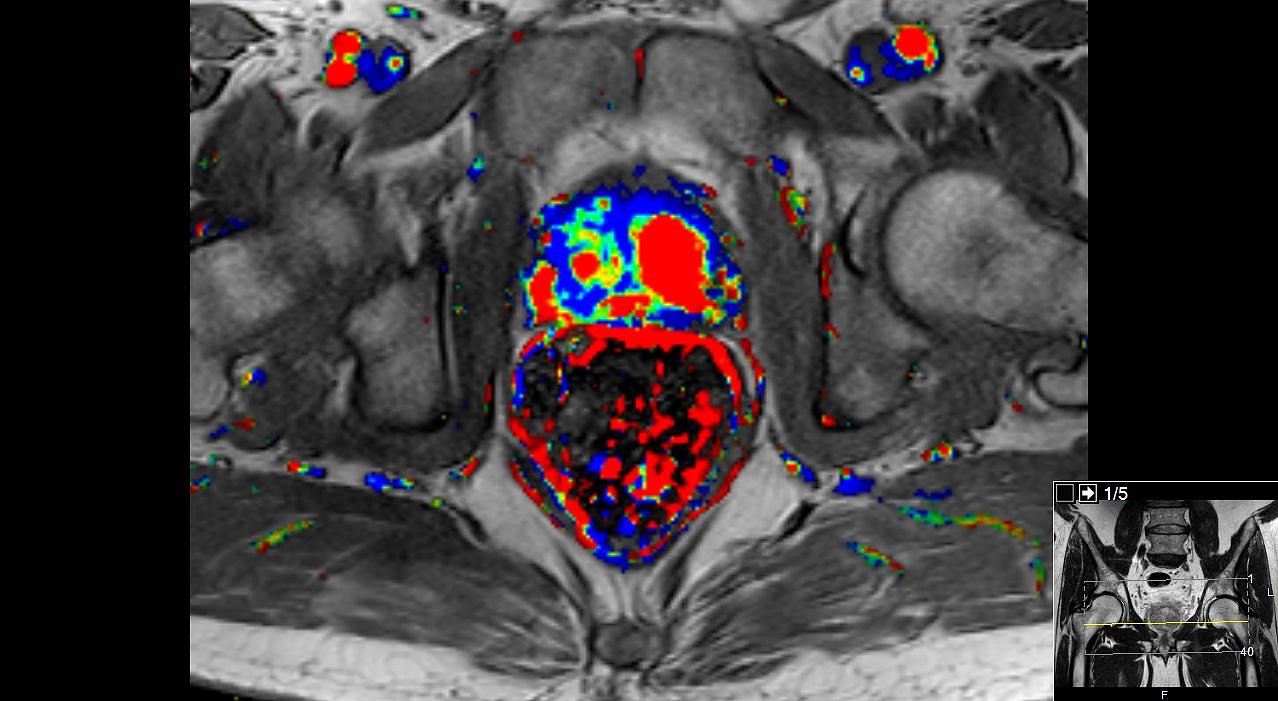

Prostata-Karzinom (Foto: Südharz Klinikum)

Tumorbeispielbild im MRT in der Dynamik und der ADC-Messung